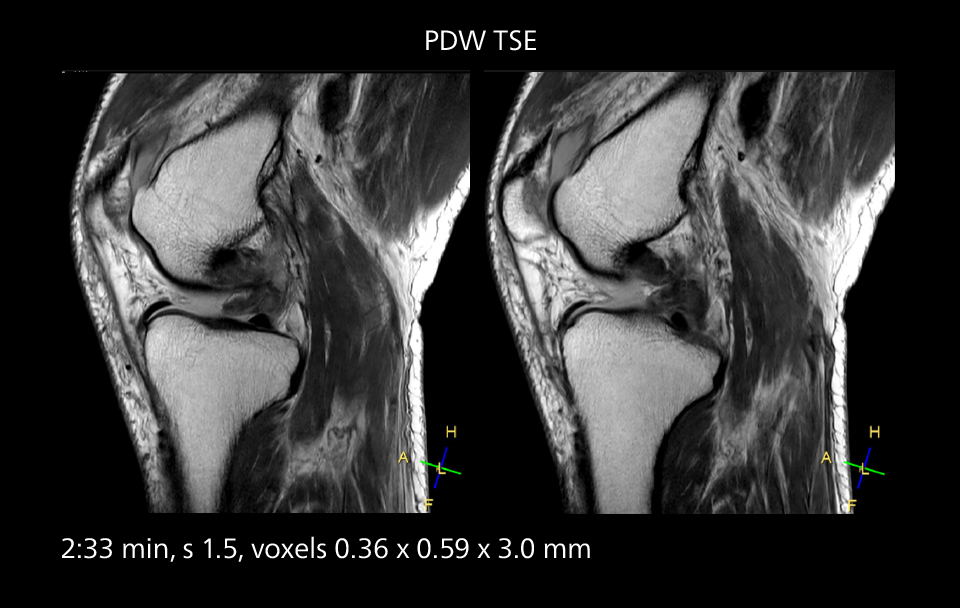

Crisp images are obtained with high resolution and short scan times using Elition X. A cyst can be seen.

Sannodai Hospital radiologists had been very satisfied with their Ingenia 3.0T with Compressed SENSE, however after acquiring SmartPath to Elition X they have demonstrated improved image quality and even higher speeds in imaging studies throughout the body, according to Dr. Makuuchi. “Generally, we were impressed by seeing that images are very sharp and have higher SNR than we used to get with our Ingenia 3.0T system,” he notes. “We were delighted to see that high image quality can be obtained in a short time thanks to the Elition with its powerful An example of increased imaging speed is in knee studies. “There is a definite scan time reduction for T2* mFFE and proton density TSE – both of these sequences benefit from much shorter repetition times,” he reports.

Overall, imaging time per sequence has been reduced since the Elition X upgrade. This can help reduce the risk of patient movement and the need for rescans. “As our hospital has many elderly patients, we consider it important to obtain high-quality data in a short time,” Dr. Makuuchi says. “Shorter imaging times are also useful for accepting emergency patients, because faster emergency studies have a reduced impact on the daily examinations schedule. In emergency cases it is also important that high quality images are obtained in a short time.”